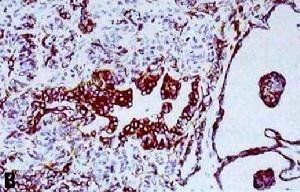

Sertoli-Leydig細胞瘤5 Keratin染色顯示出網狀區域,而鄰近的性索和間質則呈局部表達